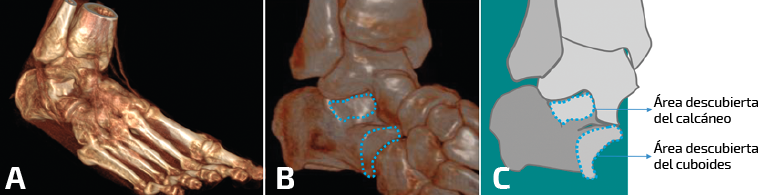

En nuestra experiencia, tras el análisis de una serie de 72 pies y tobillos estudiados mediante la TC dinámica en carga simulada tanto en voluntarios sanos como en pacientes afectos de inestabilidad crónica de tobillo, se observó que existen diferencias significativas en el rango de movilidad rotacional a través de un eje helicoidal trazado en la articulación subastragalina a partir de las posiciones extremas en inversión y eversión subtalar (Figura 4). Manteniendo el astrágalo fijo en la mortaja tibioperonea con una dorsiflexión mantenida de 10°, el calcáneo viró en mayor grado a través de un eje helicoidal en los tobillos sintomáticos cuando se compararon con el tobillo contralateral asintomático (Figura 5). Asimismo, se observó una correlación entre variables de descobertura articular en la articulación subastragalina y calcaneocuboidea en las posiciones de máxima inversión del retropié y rotación interna (Figura 6).

Figura 6. Representación volumétrica de una inversión forzada y carga simulada (A) con la representación de las áreas descubiertas del calcáneo a nivel subtalar posterior y calcaneocuboideo.